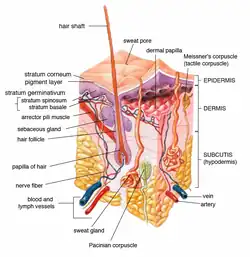

Diagrammatic sectional view of the skin (magnified)

Diagrammatic sectional view of the skin (magnified) Schema (German)